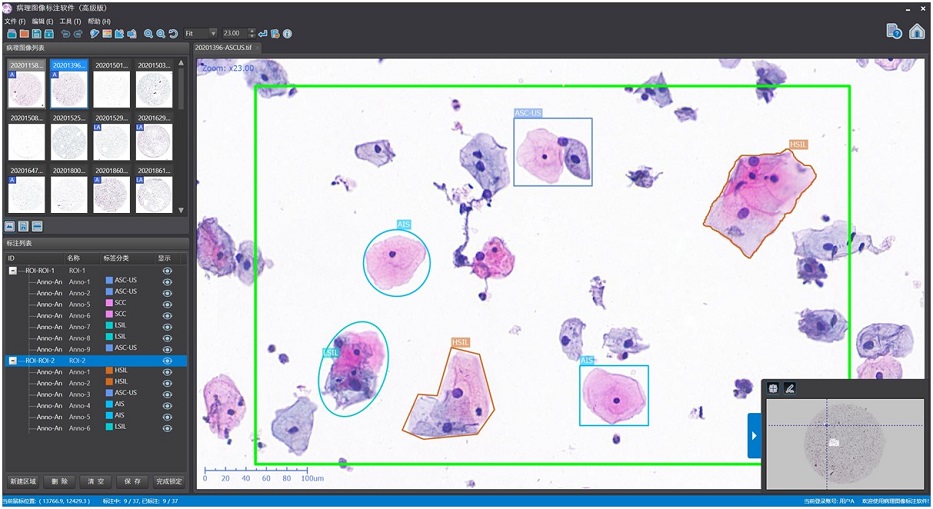

内窥图像标注软件(MISAT-Endo)

病理图像标注软件(MISAT-Patho)